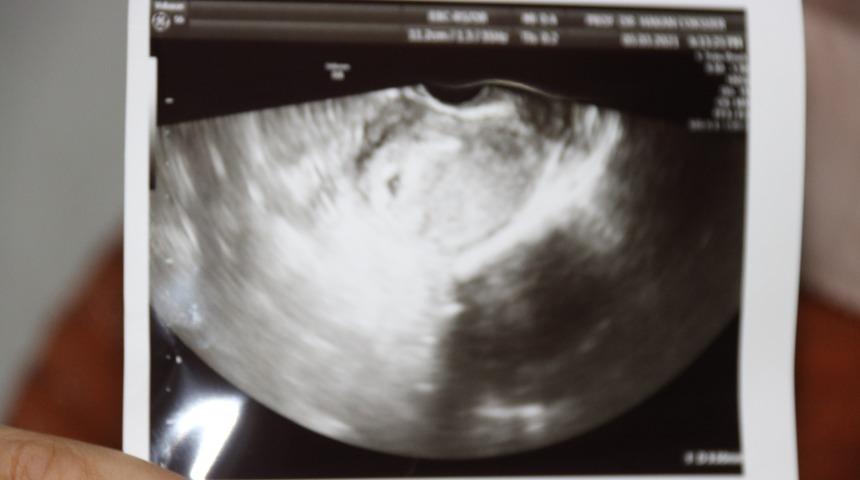

Hastaya daha önce de uygulama yapıldığını ve hiç hücre bulunamadığını belirten Prof. Dr. Hakan Çoksüer, o süreçte tüp bebek uygulamasının da iptal olduğunu söyledi. Prof. Dr. Çoksüer, "Hasta birçok merkezde tedavi almaya çalışmış fakat sperm bulunamadığı için tüp bebek uygulaması yapılamamış. Biz de, hasta kliniğimize geldiğinde ilk önce sperm detoks tedavisi yaptık. Özellikle spermin daha iyi gelişim sağlayabilmesi için. Destoks tedavisinden sonra biz tüp bebek yapmaya karar verdik. Çünkü hastaya baktığımızda hastanın hiç spermi yoktu. Tüp bebek yaptıktan sonra yumurtaları aldığımız esnadan sonra mikro TESE uygulaması yaptık. Mikro TESE'de öncü hücreleri aldıktan sonra Rosi uygulaması yöntemi uyguladık. Rosi yöntemi Japonya’da uygulanmaya başlanmış. Artık son yıllarda bizim ülkemizde yapılıyor. Biz de kendi kliniğimizde Rosi yöntemiyle tüp bebek uygulaması yaptık. Rosi yöntemi sonrası gebelik elde ettik. Tabi bu esnada hastamızın stresi fazla olduğu için biz akupunktur tedavisi yaptık. Akupunkturla hem stresi azalttık hem yumurta kalitesini artırdık. Sonrasında biz transferimizi gerçekleştirdik. Embriyoların gelişimi iyi oldu ve embriyolarımız beşinci güne kadar gitti. Çünkü burada embriyoların da kaliteli olması bizim açımızdan önemli. Transfer sonrası sonucumuzu aldık. 12’nci günde de test yaptığımızda test sonucu pozitifti. Bugün de ultrasona baktığımızda gebelik kesesi gördük. Gebelik kesesini gördükten sonra hasta gözlerine inanamadı. Çünkü hastaya daha önce, hiç hücre olmadığı için imkansız olduğu söylenmiş. Doğru tedavi, doğru merkez, doğru uygulama başaranın ana anahtarıdır" dedi.